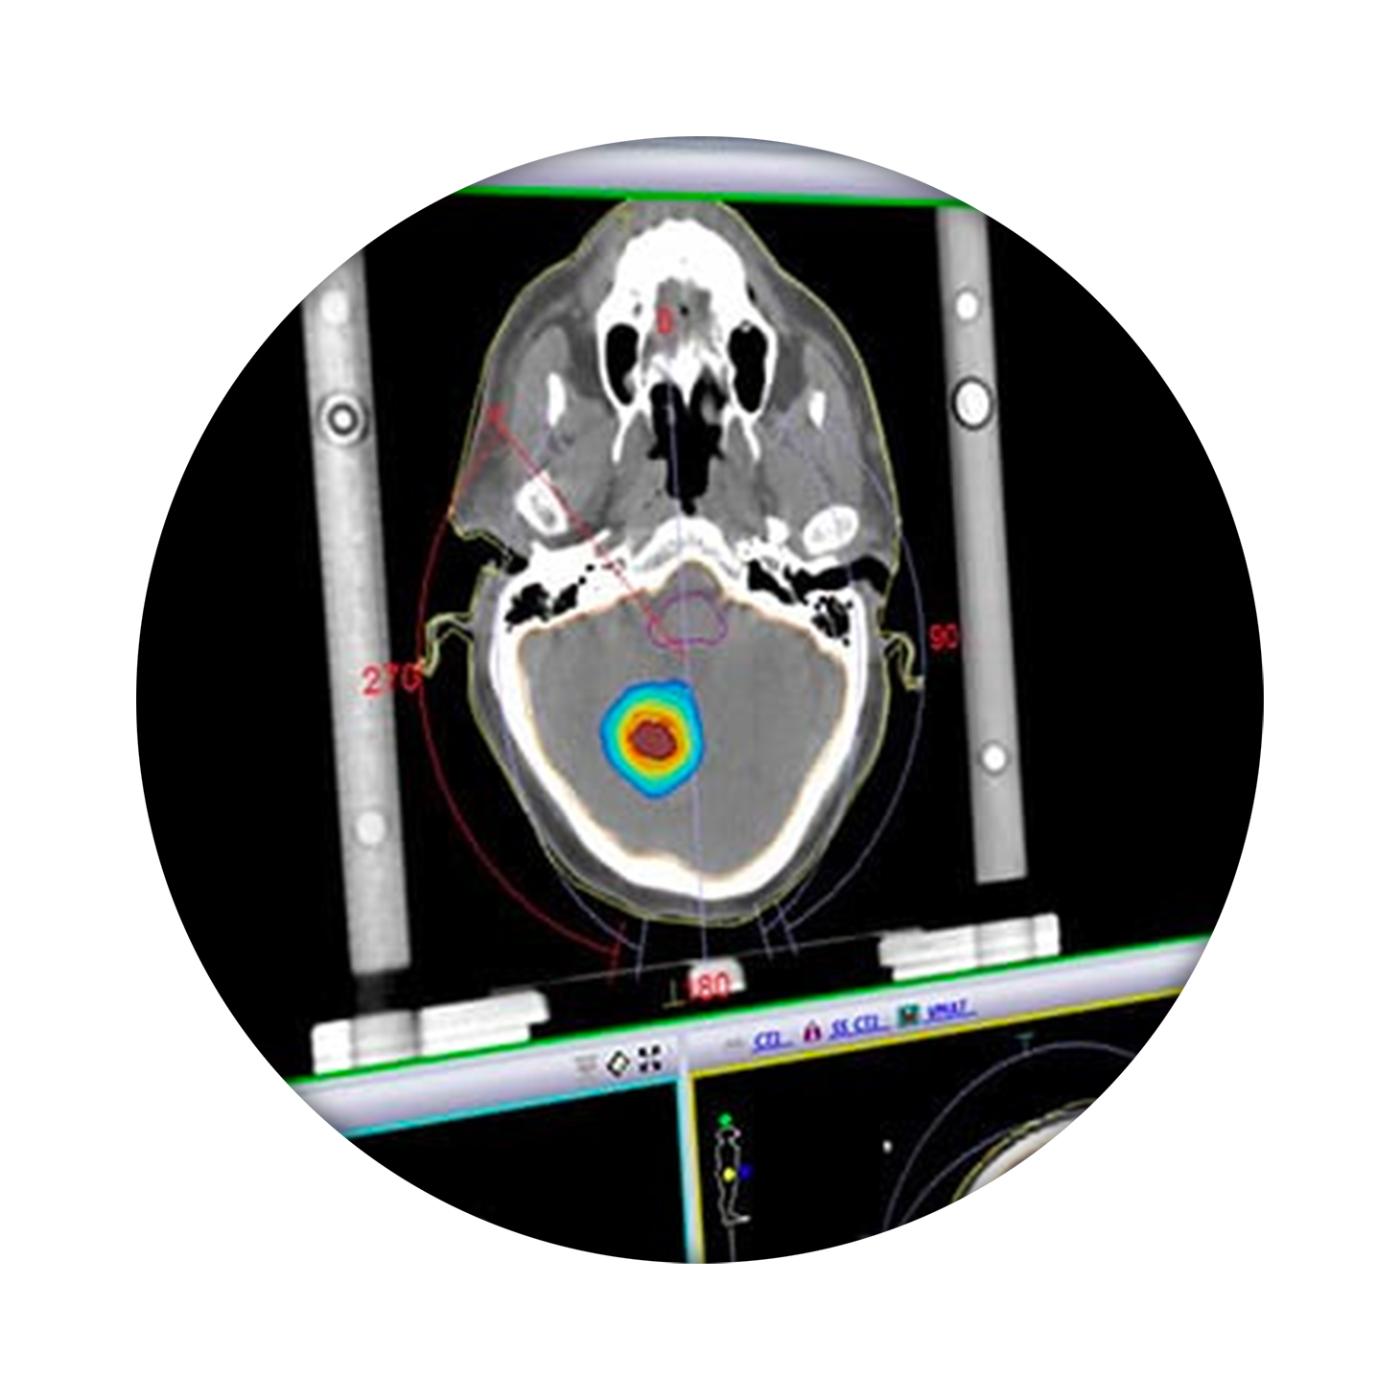

我科 Elekta Monaco 治疗计划系统 发布时间:2018/7/5 4:10:00       浏览次数:5197次

Monaco帮助临床医生提供最高标准的治疗。利用生物智能和标准化的计划解决方案,Monaco帮助临床医生了解患者生物学状态,同时提供快速有效的计划设计方案,将优化后的计划提交到治疗流程。